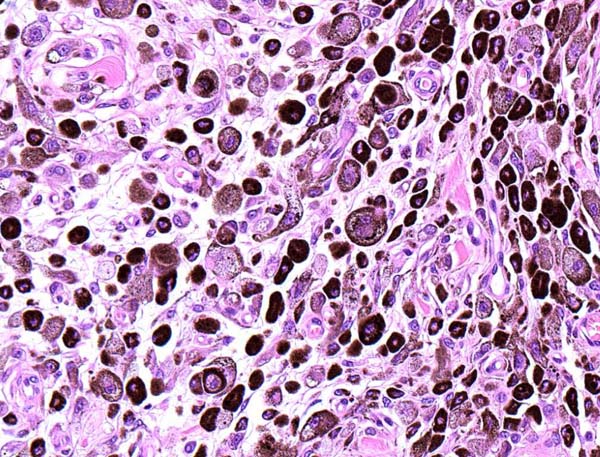

右目の瞼にできたデキモノを気にされて来院されました。切除手術を行い元気に退院しました。病理組織検査の結果は良性の「黒色細胞腫」でした。病理コメント:メラニン産生細胞に由来する腫瘍です。腫瘍細胞はやや高い細胞異型性を示しますが、高倍率10視野における核分裂数が3個を越えていないため良性と判断しました。切除マージンは確保されていますが、念のため今後の経過にはご注意ください。